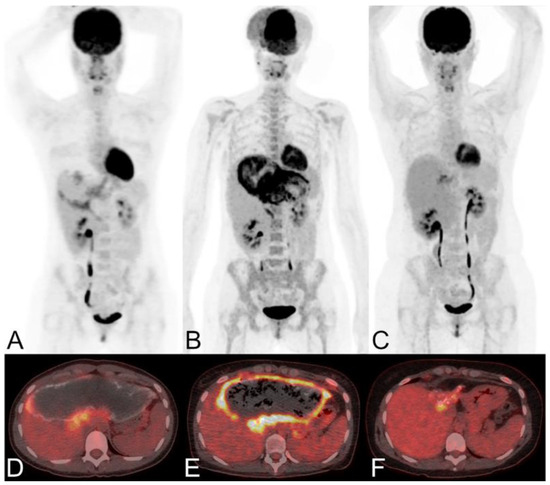

FDG-PET is also used for long-term follow-up of AE (Figure 10). The absence of metabolic activity indicates suppression of parasite activity, which is not equivalent to parasite death. This suppression can persist for several years, and oral medication therapy should be reinitiated when recurrence is detected by PET [167,168,169]. In a retrospective study of 179 AE patients who underwent PET/CT scans, it was found that as the clinical status progressed, significant changes occurred in total immunoglobulin E (IgE), parasite-specific IgE, and serological status (using crude antigen preparations or recombinant/purified antigens such as EM10, Em18, and Em2) [170]. Notably, these serological biomarkers were also significantly higher in patients with positive PET results. Multiple studies have shown that combining FDG-PET with serological testing can further improve the accuracy of parasite activity identification [171]. For patients with AE who are unable to undergo surgical resection, oral albendazole treatment is often prescribed; the treatment usually is life-long. For patients with inactive disease, a structured treatment interruption (STI) of drug therapy may be a goal, not only to save costs but also to improve quality of life. Ammann et al. [172] evaluated FDG-PET/CT and antibody levels against recombinant Emll/3-10 antigen as markers of parasite vitality, serving as a reliable tool to allow for the selection of patients who can safely discontinue chemotherapy with a low risk of AE recurrence. Husmann et al. [173] hold the view that negative FDG-PET/CT results combined with no detectable levels of Em-18 antibodies may allow for the safe discontinuation of benzimidazole therapy in patients with AE. The quantitative imaging parameter SUVratio, obtained through PET/CT, correlates with the time to reach no detectable levels of Em-18 antibodies and the duration of benzimidazole treatment. In patients presenting negative results for both indicators, a watch-and-wait strategy might be permissible [174].